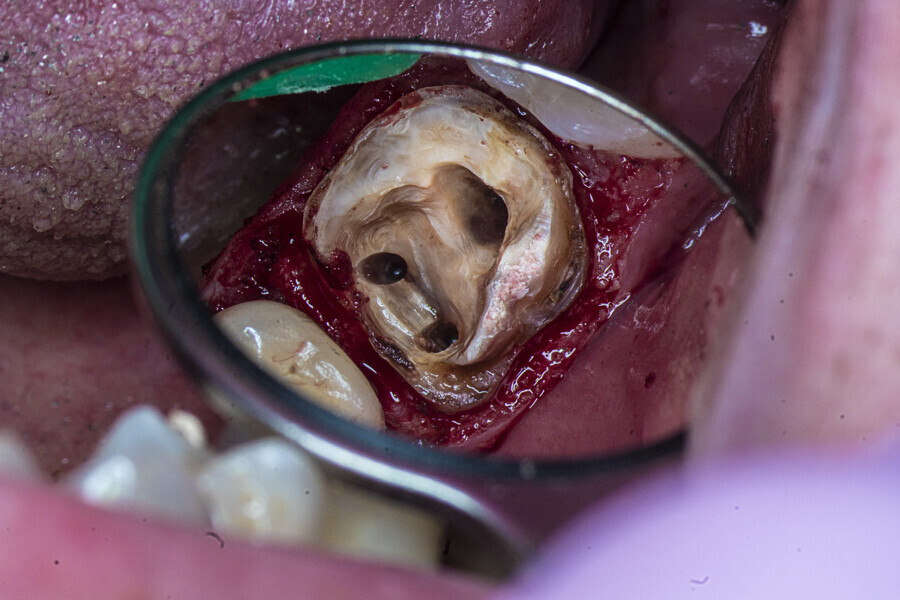

The patient was referred to Dr Karaś’s office for non-surgical root canal retreatment of tooth #46. The tooth was symptomatic, and the radiographic examination revealed a periapical lesion around the mesial root. The periapical lesion was clearly visible, but the shape of the root canal was not clear (Fig. 22). The examination was extended by CBCT imaging. The CBCT scan revealed internal resorption in the mesiobuccal canal and an isthmus and apical inflammatory root resorption in the apical area of the mesial root (Fig. 23). A cast post and prosthetic crown were also noted.

Two treatment plans were presented to the patient, non-surgical root canal retreatment and surgical root canal retreatment. After intra-oral examination, the quality of the prosthodontic treatment was found to doubtful (Fig. 24). The decision was made to remove the crown and perform non-surgical retreatment.

After local anaesthesia, the crown was cut with a high-speed handpiece (Fig. 25). The post was exposed and removed (Fig. 26 & 27). The pulp chamber and root canal orifices were examined for cracks. After inspection, a gingivectomy was performed (Fig. 28) and a dental dam (Kerr Dental) was placed (Fig. 29). The dental dam was sealed with a temporary flowable material (Fig. 30). After sealing the dental dam, the full adhesion protocol with a sixth-generation self-adhesive primer and bonding agent was performed, and the pre-endodontic build-up was created (Fig. 31). Residues of the cement and root canal filling materials were removed with a diamond-coated ultrasonic tip (Woodpecker; Fig. 32). Patency was easily established with hand files (VDW), and the canals were shaped with rotary martensitic files (Poldent) up to 40/0.04. Each step of instrumentation was performed with lubricating cream containing EDTA (VDW; Fig. 33). After each instrument, the canals were flushed with 5.25% sodium hypochlorite (Cerkamed). After reaching the final sizes of the root canals, the irrigation protocol was performed: three sequences of 5.25% sodium hypochlorite and 40.00% citric acid (Cerkamed) activated with an ultrasonic file (MANI), followed by 5.25% sodium hypochlorite activated with the ultrasonic file for approximately 10 minutes (Figs. 34 & 35). The flow of the liquid between both mesial canals was visible.

At this stage, one of the most important decisions had to be made regarding the resorption and isthmus present in the mesial root. On the one hand, in the case of non-penetrating internal resorption, the material of choice is gutta-percha with a sealer. On the other hand, in the case of apical inflammatory root resorption, it is recommended to use mineral trioxide aggregate (MTA) or putty materials. There is no problem with using these two materials in the same root in most cases, but in this case, the canals were too narrow to use the MTA comfortably and the quality of filling of the isthmus that could be achieved was questionable.

From this point of view, a novel approach of placing a tricalcium silicate-based sealer was a promising idea. The sealer was placed in the previously described manner. The premixed sealer in the plastic syringe (Meta Biomed) was placed in the mesiobuccal canal and the syringe depressed until it filled the mesiolingual canal. The distal canal was filled separately. In each canal, pistons from the previously heated gutta-percha extruder were placed and the warm gutta-percha was slightly compacted with stainless-steel hand condensers. A periapical radiograph was taken to evaluate the quality of the obturation. The bioceramic sealer was slightly extruded through the resorbed apex into the periapical area (Fig. 36). After the obturation, the chamber and orifices were cleaned (Fig. 37). A resin core with fibre posts was placed, and the temporary pink material was removed. The patient was referred to the prosthodontist for final restoration.